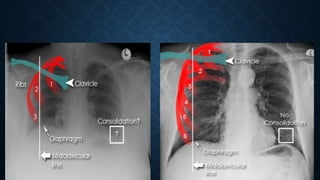

This document provides an overview of x-rays for medical students, covering topics such as ensuring x-rays are well-aligned, exposure levels, common artifacts and anatomical features, abdominal x-ray positions and views, and specialized x-rays including barium swallows, enemas, and tests to examine the esophagus, small bowel, biliary tree, and kidneys.